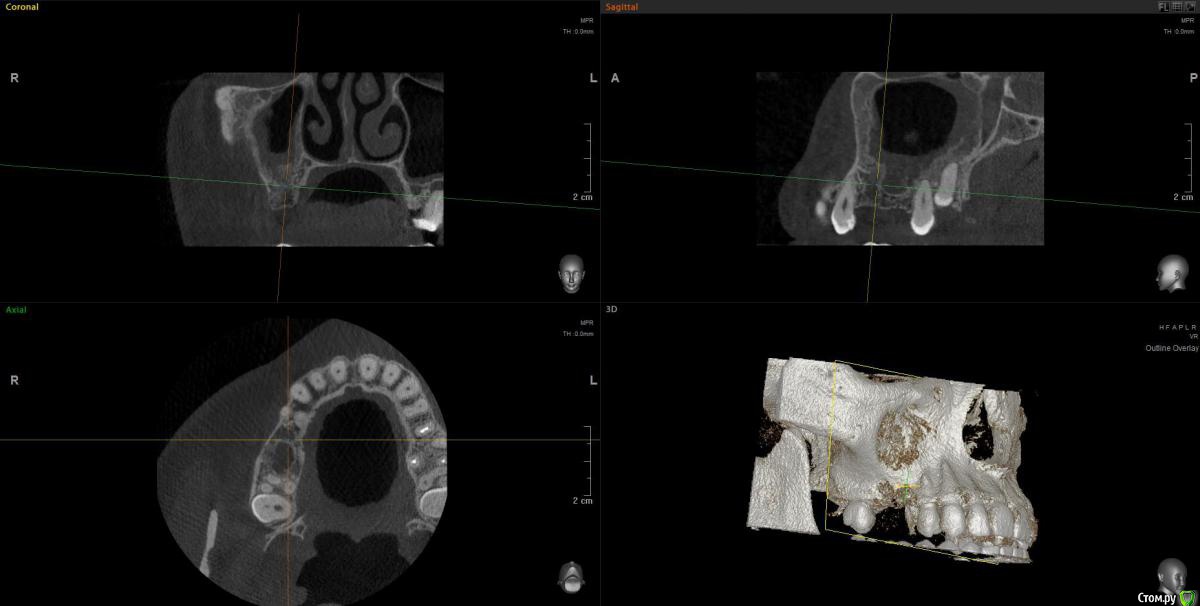

wladdX Опубликовано 30 июня, 2020 Поделиться Опубликовано 30 июня, 2020 Несколько скриншотов из КЛКТ 2 Ссылка на комментарий

колесников Опубликовано 30 июня, 2020 Поделиться Опубликовано 30 июня, 2020 Есть жидкость в пазухе на момент снимка. Можно только предполагать что является причиной воспаления,полной картины нет. Возможно это рельеф дна пазухи. В области 6ки углубление,где как в колодце застаивается слизь и прочее что попадает в полость и естественного дренажа не происходит. Я бы рекомендовал поставить 2 импланта 5,6. В области 6го провести закрытый синуслифтинг. Рельеф дна пазухи выровняется и вероятно обострений больше не будет. По крайней мере процессы происходящие в пазухе никак не повлияют на имплантацию,тогда как имплантация может купировать процессы в пазухе. Ссылка на комментарий

Оvzaika Опубликовано 1 июля, 2020 Автор Поделиться Опубликовано 1 июля, 2020 Несколько скриншотов из КЛКТ 25_1.jpg25_2.jpg26_1.jpg26_2.jpgH_M.jpgСпасибо! Ссылка на комментарий